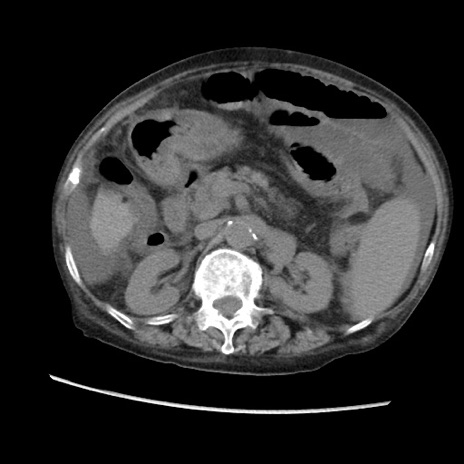

症例31(横断像)

【症例】80歳代 女性

【主訴】腹部膨満感

【現病歴】他院にて肝硬変にてフォロー中。1週間前から便秘、腹部膨満感、臍部腫瘤あり受診となる。

【既往歴】肝硬変

【身体所見】腹部膨隆あり、皮膚変化なし、疼痛なし。

【データ】WBC 4600、CRP 0.25